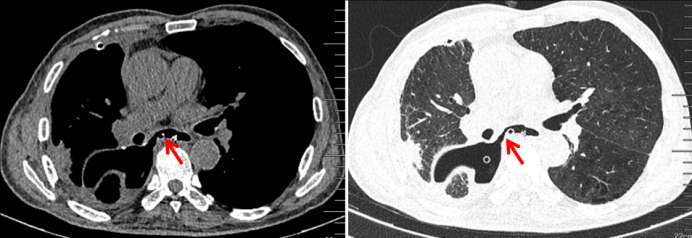

2024年2月18日,患者于外院体检,胸部CT示:右肺下叶内基底段肿块影(3.4 cm×3.0 cm)(图1)2024年2月29日,我院CT引导下经皮肺穿刺,病理证实为鳞状细胞癌。2024年3月11日,PET-CT示:右肺下叶鳞状细胞癌伴肺门纵隔内淋巴结转移(cT4N2M0ⅢB)。2024年3月16日予TP(紫杉醇+顺铂)+替雷利珠单抗治疗3个周期。7月9日复查胸部CT,可见原有肿块明显好转(图2)

图片

1  患者外院胸部CT(2024-02-18)

2   复查胸部CT(2024-07-09)